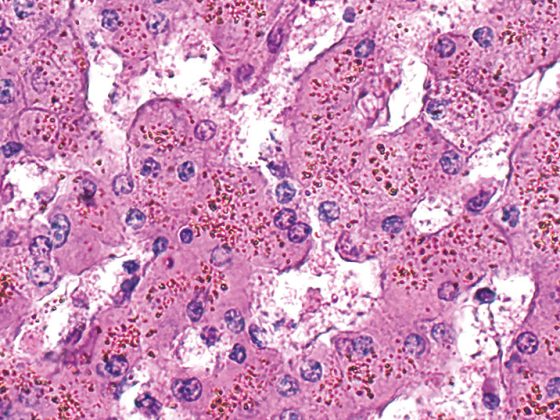

Rund die Hälfte aller Diabetiker entwickelt eine chronische Nierenerkrankung. Es hat sich gezeigt, dass SGLT-2-Hemmer nicht nur den Glukosestoffwechsel günstig beeinflussen, sondern auch Herz und Nieren schützen. Der nephroprotektive Benefit von Dapagliflozin konnte in der DAPA-CKD-Studie eindrucksvoll belegt werden. In einer kürzlich präsentierten Sekundäranalyse dieser Studiendaten zeigte sich, dass die nierenschützenden Effekte bei Typ-2-Diabetikern mit unterschiedlich ausgeprägter Makroalbuminurie ähnlich waren.